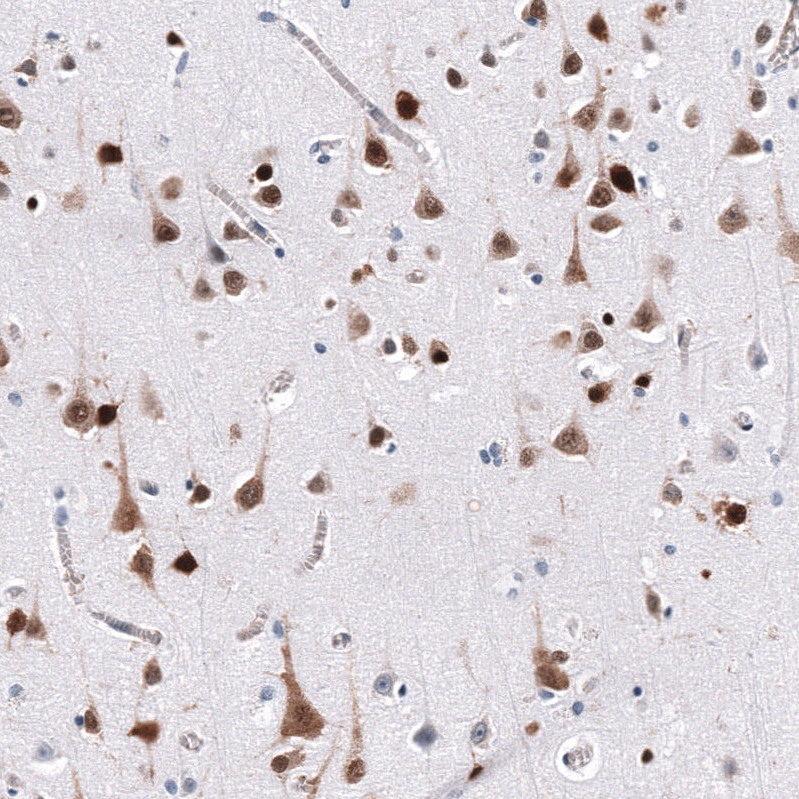

Immunohistochemistry analysis in human cerebral cortex and skeletal muscle tissues using AMAb92027 antibody. Corresponding ELAVL2 RNA-seq data are presented for the same tissues.